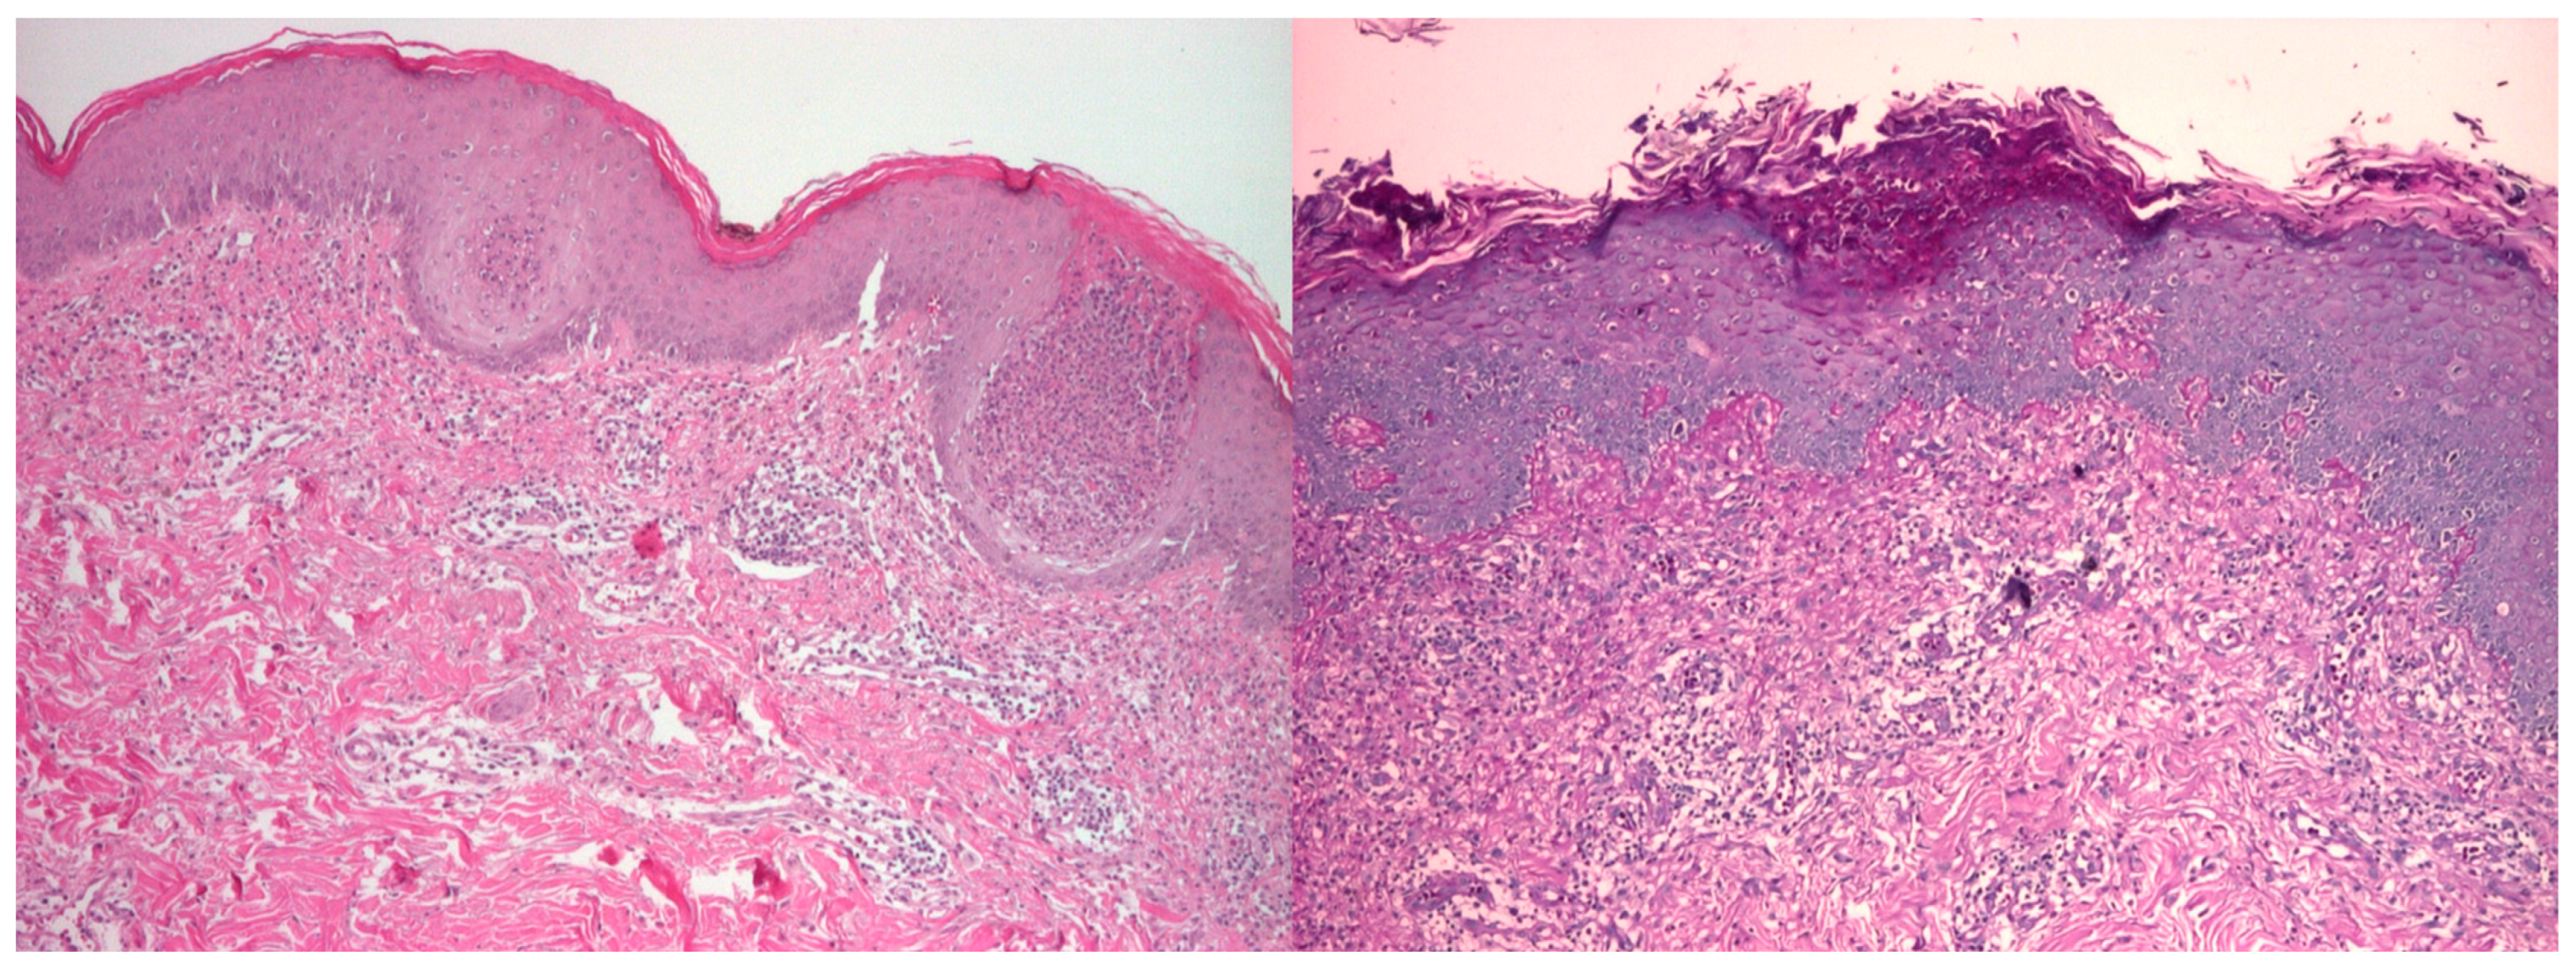

2.3. Histopathology and Additional Workup

| Histopathology | Interface dermatitis, basal vacuolar degeneration, dermal mucin deposition | Similar findings, but often with more prominent inflammation and vasculopathy |